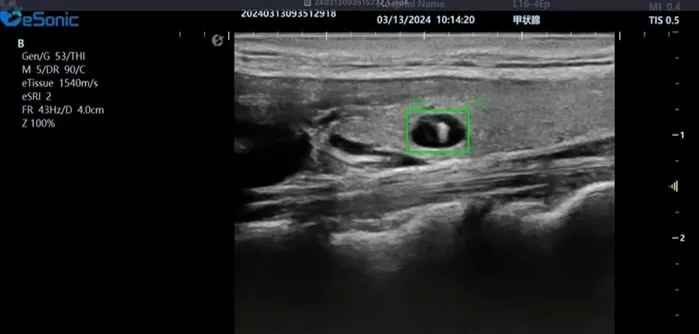

利来国国际网站医疗(ESI)表示,其最新的人工智能功能可以帮助到医疗机构的工作效率,功能包括,实时、动态、快速自动识别病灶,良恶性病灶概率预测,甲状腺结节和乳腺的二维灰阶动态自动实时检测需求,提供多个结节动态检测轮廓框。实时获取多幅具备临床特征(大小、属性等)的结节切面,同时提供当前切面所示结节的结节大小、属性特征、TI-RADS 分级。

对于甲状腺结节相关的自动检测功能,甲状腺结节病灶检出率≥95%,良恶性分类灵敏度≥90%、良恶性分类特异度≥85%。